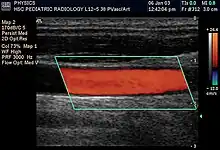

Renal ultrasonography using duplex technique of a normal adult kidney, with the estimation of the systolic velocity (Vs), the diastolic velocity (Vd), acceleration time (AoAT), systolic acceleration (Ao Accel) and resistive index (RI). Red and blue colors in the color box represent flow towards and away from the transducer, respectively. The spectrogram below the B-mode image shows flow velocity (m/s) against time (s) obtained within the range gate. The small flash icons on the spectrogram represent initiation of the flow measurement.

Doppler ultrasonography is widely used in renal ultrasonography. Renal vessels are easily depicted by the color Doppler technique in order to evaluate perfusion. Applying spectral Doppler to the renal artery and selected interlobular arteries, peak systolic velocities, resistive index, and acceleration curves can be estimated (Figure 4) (e.g., peak systolic velocity of the renal artery above 180 cm/s is a predictor of renal artery stenosis of more than 60%, and a resistive index, which is a calculated from peak systolic and end systolic velocity, above 0.70 is indicative of abnormal renovascular resistance).[12]